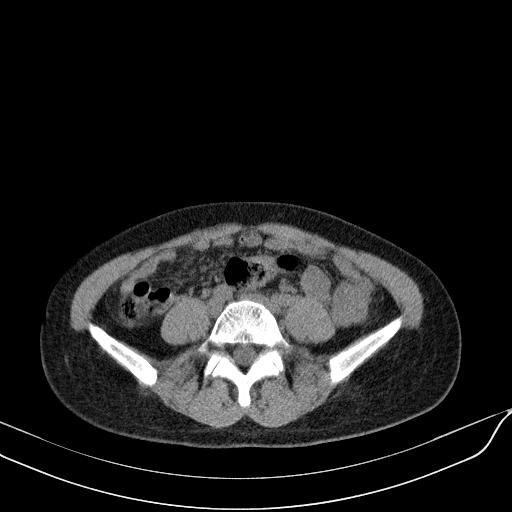

标题: CT23965:无外伤史,下腹痛 [打印本页]

标题: CT23965:无外伤史,下腹痛

肠道未准备,继续往下扫,乙状结肠占位不排除。建议钡灌或结肠镜检查。

乙状结肠占位不排除

未见明显异常改变,做个气钡双重造影除外一下结肠病变,无外伤史为啥不常规喝泛影葡胺水对比剂再扫ct呢?

扫描时应做肠道准备,口服稀释造影剂。

回肠间质瘤?

肠道肿瘤,建议行钡剂灌肠检查。